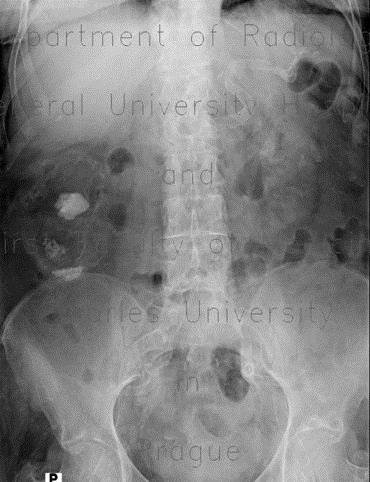

رادیولوژیک